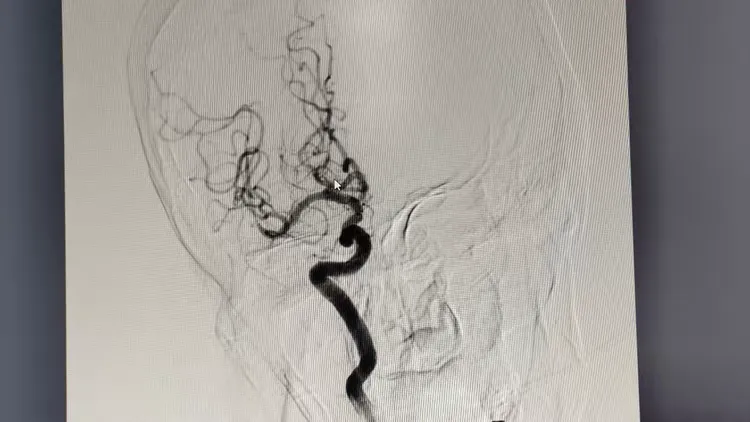

挑战远未结束。患者病变部位位于右侧大脑中动脉M2段下干起始段,该区域血管走行迂曲、解剖结构复杂,且操作空间狭小,手术难度较大。凭借十余年临床积淀的精准操作经验,龙发青书记亲自主刀,带领团队在DSA(数字减影血管造影)引导下,精准操控微导管穿越血管迷宫,抵达闭塞核心区域,释放取栓支架一次性完整捕获并取出栓子。术后即时造影显示,闭塞血管血流通畅率达100%,缺血脑组织血供成功恢复。后续通过抗血小板聚集、调脂稳斑、神经保护及早期康复介入的个体化综合治疗,患者出院时左侧肢体肌力恢复至4级以上,已能独立行走、生活自理,重归正常生活轨迹。

↑患者取栓后造影图像